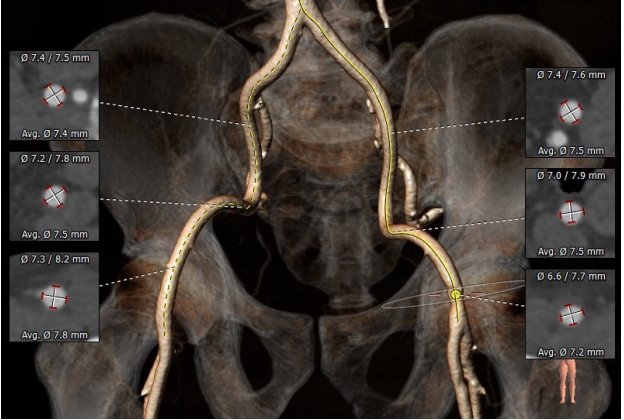

患者为Type0型二叶瓣,瓣叶明显增厚,中度钙化,法式窦结构不大,双冠高度可,初步判断冠脉风险低,升主动脉明显增宽,左室大小正常,主动脉弓部走行较平缓,推荐右侧股动脉为主入路。

选用启明VenusA L29瓣膜,考虑Type0型二叶瓣的特殊狭窄情况选择稍高位释放,释放位置良好

患者为Type0型二叶式主动脉瓣,瓣膜钙化分布不均匀,导致两个瓣叶出现贴合不良的状况,从而使导丝跨瓣异常困难,为我们今后进行导丝跨瓣积累了丰富经验。患者瓣口严重狭窄,瓣膜释放过程中容易因挤压导致瓣膜下移,应注意从稍高位置开始释放并注意调整位置。人工瓣膜植入后即刻跨瓣压差由术前140mmHg减少为1mmHg,再行主动脉根部造影后提示瓣膜置入位置良好、形态完整,未见瓣周漏,未出现相关并发症。